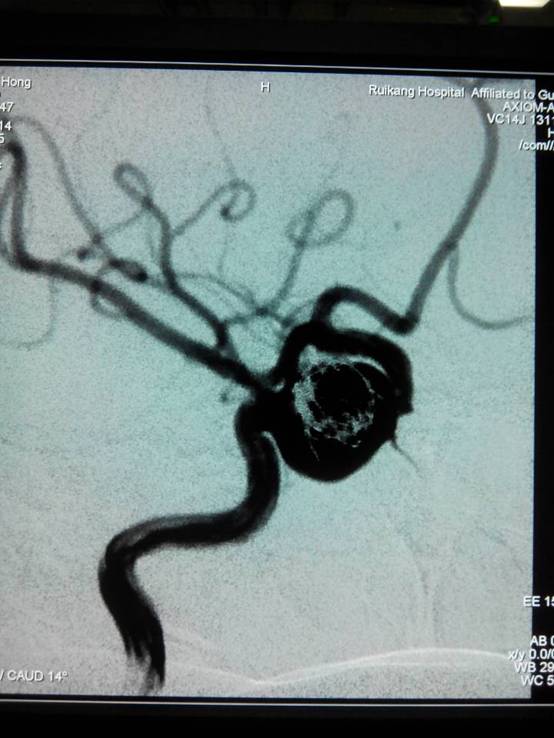

经神经外科主任范学政博士及副主任黄进能等多位专家会诊,确诊为左颈内动脉海绵窦段巨大动脉瘤,在经患者家属同意后,医院神经外科专家经过讨论,迅速制定了手术和麻醉方案,3月23日,吴英被推进了手术室。3个小时后,动脉瘤被成功栓塞,吴英的脑部警报顺利解除。

黄进能主任介绍,“脑动脉瘤就像埋在我们大脑里的不定时炸弹,平日里多相安无事,一旦破裂将会危及生命。”动脉瘤第一次出血的死亡率约30%,短期内第二次再破裂出血死亡率高达70%~80%。更为重要的是,在所有脑卒中当中,动脉瘤破裂的死亡率及致残率都是最高的。因此,大众应高度重视,及时铲除这个潜伏在脑内的隐形杀手。动脉瘤引起的头痛多为中年以后出现类似偏头痛的发作,无周期性,部分患者可出现动眼神经麻痹或其他脑神经症状,可有蛛网膜下腔出血史,脑血管造影可确诊。